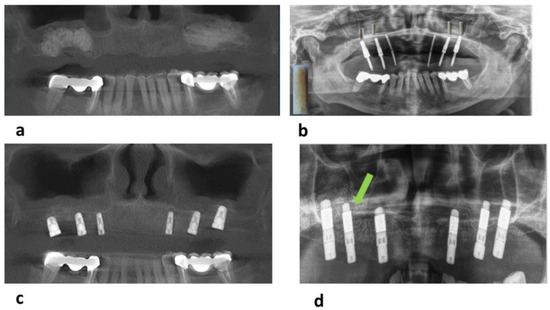

3.2. Radiological Findings